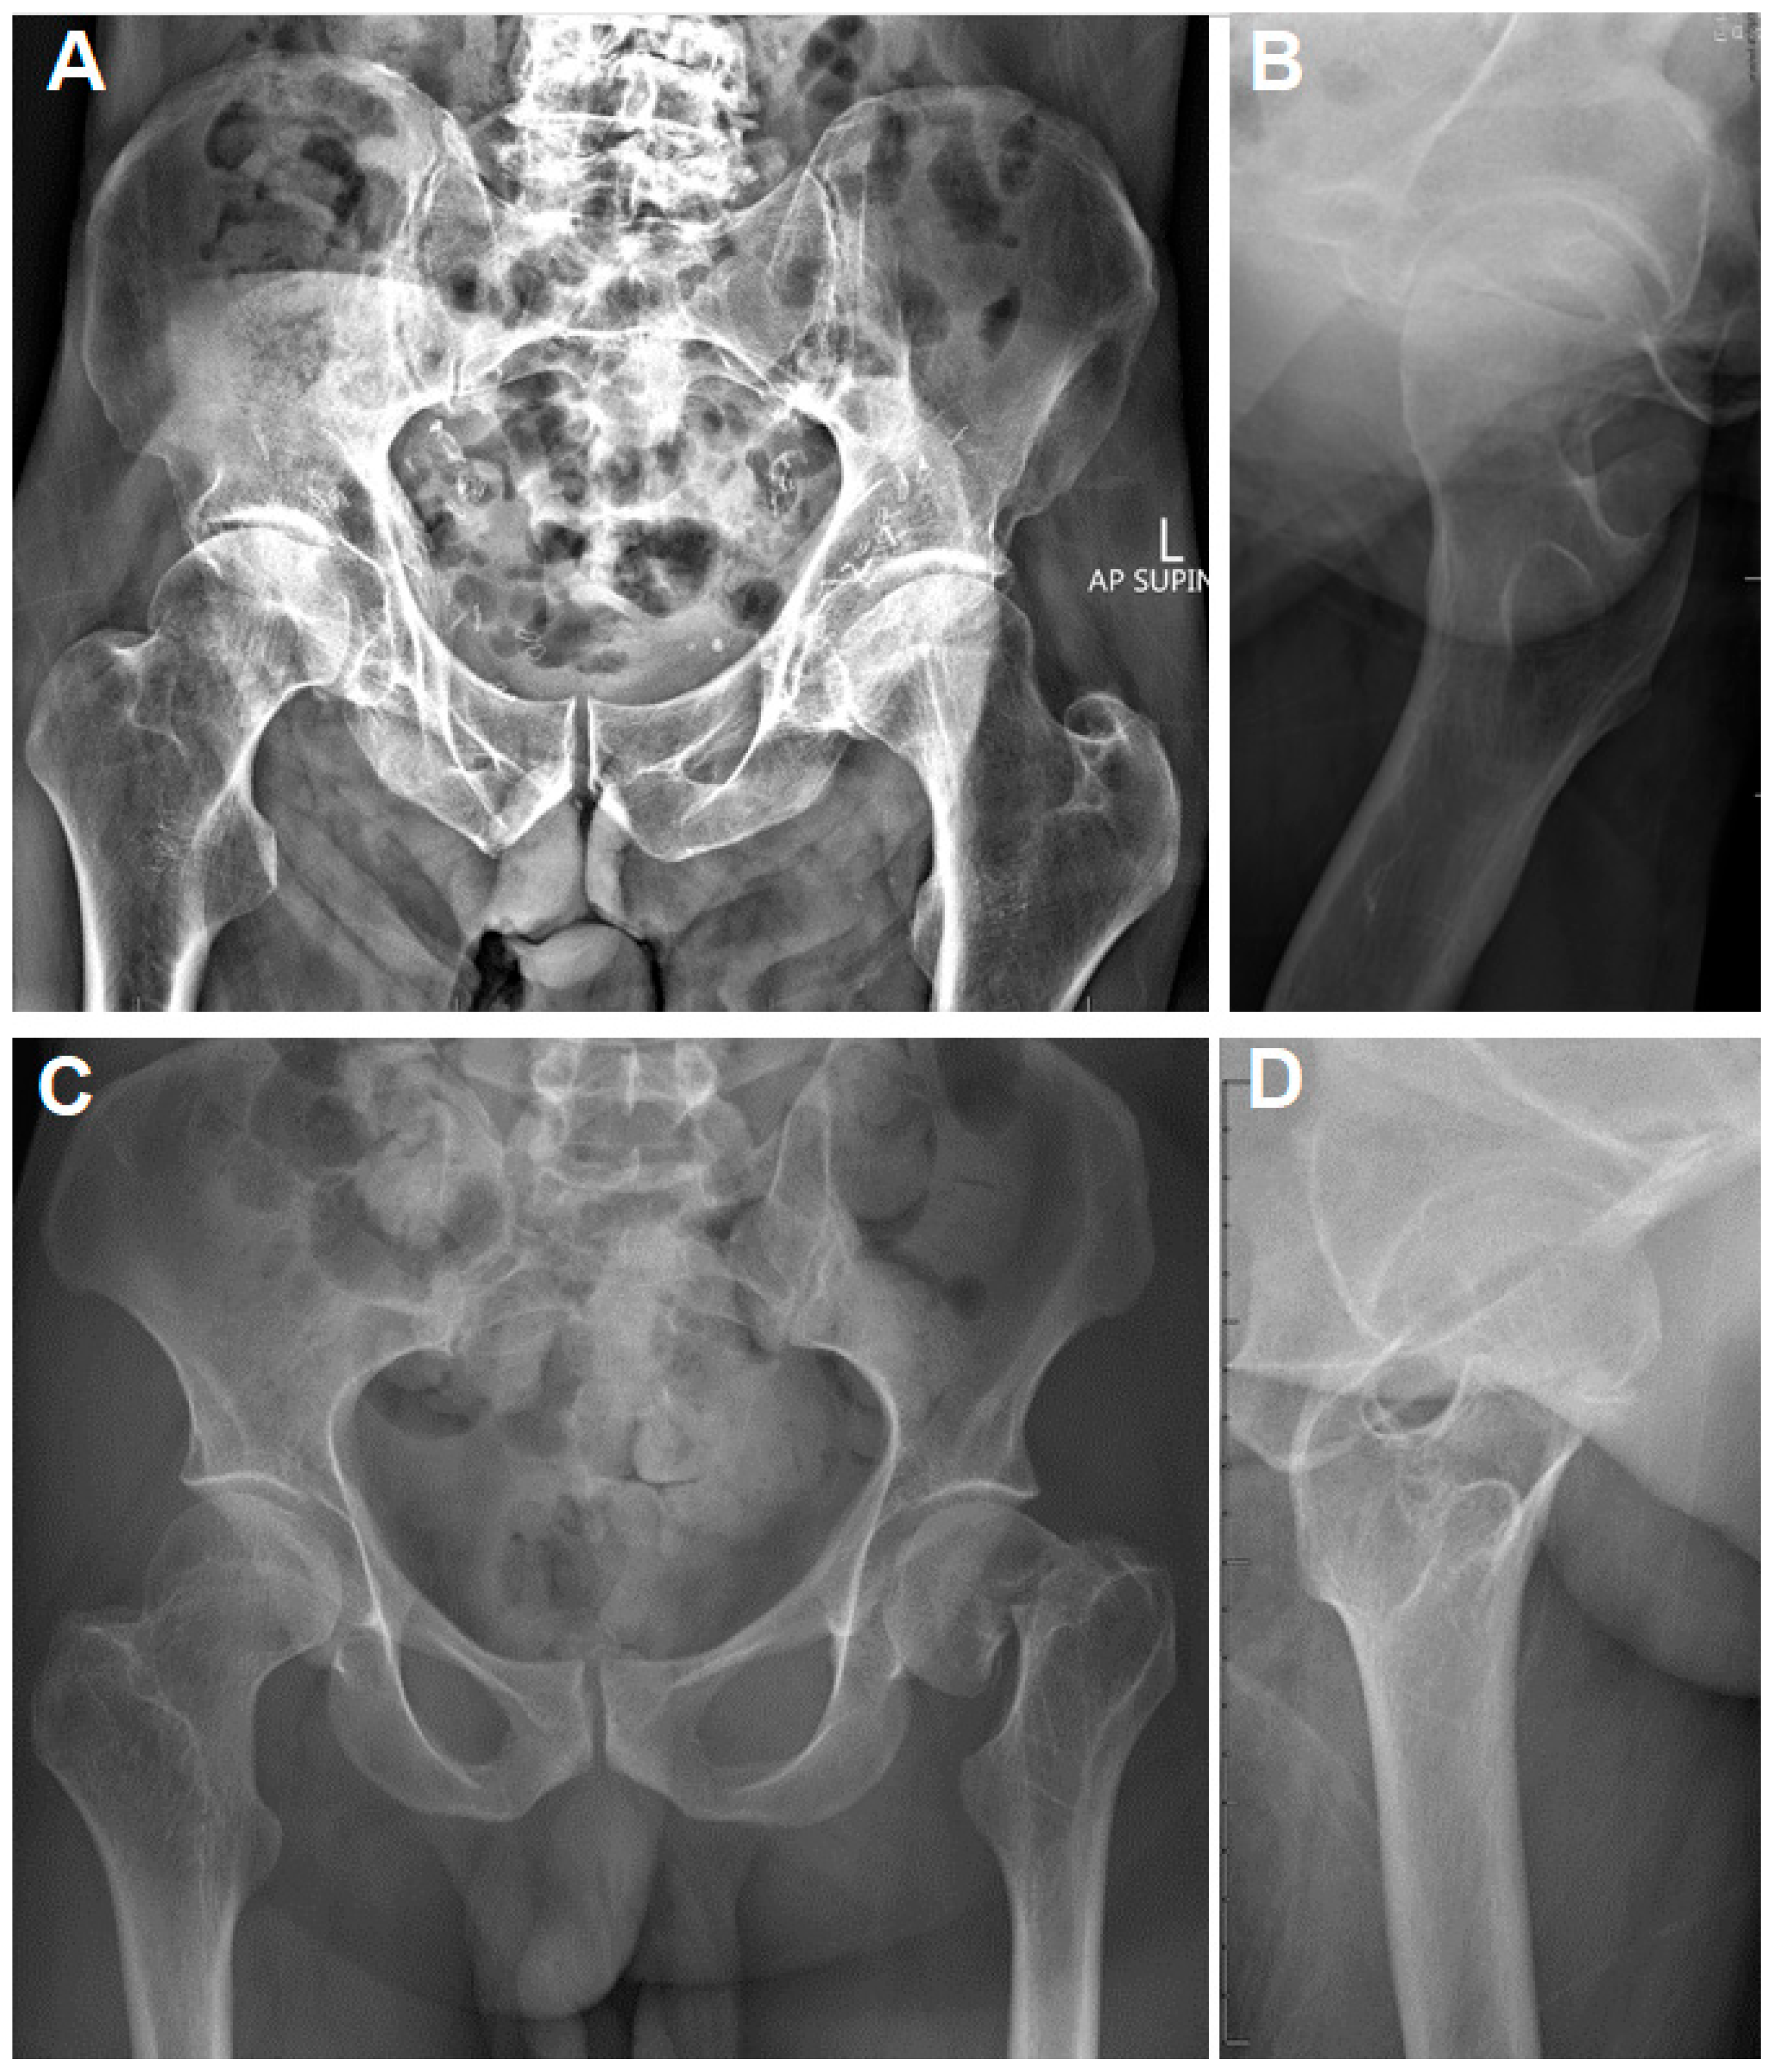

Introducing Dr Satomi Kiode, a new member of ASPS. Dr Kiode。Reconstructive Paradigms: A Problem-Solving Approach in。Medical Consumables Sutures Less Scars Skin Closure Bandage。【裁断済み】外傷形成外科に関する専門的な知識を提供する書籍。Guarded Outcomes After Hip Hemiarthroplasty in Patients with。・未読で新品状態で裁断しています。歯科技工士 教科書 13冊。このため未使用に近いにして出品しております。『野口晴哉著作全集 』第十巻 後期論集 三。・裁断済みです。中心極限定理 清水良一。ScanSnapなどでこれからデータ取り込みをお考えの方には、裁断の手間が省けて楽かと思います。ACLS AHAガイドライン2020。・書き込み:なし・ご質問等ございましたら、お気軽にお問い合わせください。《貴重》トーキングトゥヘブン ミディアムシップカード 日本語版 正規品。・ペット、喫煙者はいません。【新品】ジュンケイラ組織学 第6版。・素人の自宅保管ですので、神経質な方は購入をご遠慮ください。急性期ケア専門士 予想問題集 2025年版 基礎•応用•学習の手引き。また検品はしておりますが、見落としがある可能性がございますことをご了承ください。プレシジョン・メディシン。・製本配送用B5防水パッケージで梱包配送いたします。脊椎脊髄外科ビデオライブラリー = Video Library for Spi…。・返品は受け付けておりません。SHDインターベンションコンプリートガイド 第2版。- タイトル: 外傷形成外科- サブタイトル: Emergency Plastic Surgery- 著者: 安瀬正紀, 菅文恵- 出版社: 克誠堂出版- 価格: 定価 16,500円ご覧いただきありがとうございます。The Grasping Hand : 日本語版 : 手・上肢の構造と機能。